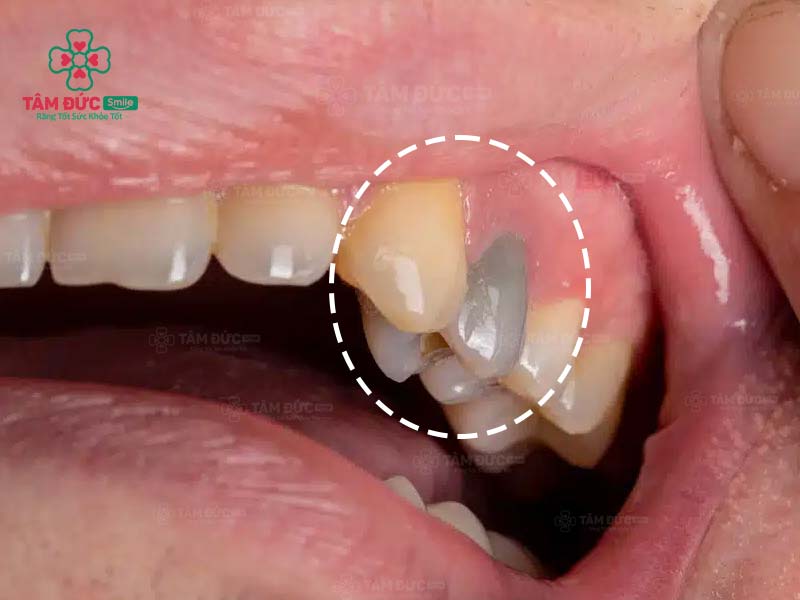

3. Khi răng chết tủy có màu gì?

Chết tủy răng là bệnh lý thường gặp, khi răng bị chết tủy sẽ có màu tím nhạt hoặc nâu đen tùy theo mức độ khác nhau. Nguyên nhân là do máu viêm trong tủy ngấm vào ngà răng làm thay đổi màu sắc thân răng.

Răng bị chết tủy thường đi kèm với bệnh lý sâu răng. Thân răng thường có màu nâu đen do vi khuẩn phá huỷ các thành phần của răng.

Để ngăn chặn diễn biến nghiêm trọng, Quý khách nên lưu ý màu sắc thân răng, cần can thiệp ngay khi thấy răng có đốm nhỏ màu đen. Điển hình là khi thấy răng chuyển từ màu trắng ngà sang hồng nhạt, đây là dấu hiệu cảnh báo buồng tủy bị chấn thương. Trường hợp này vẫn có thể chữa tủy nếu áp dụng đúng cách, đúng lúc. Nếu không, tủy răng sẽ chuyển sang màu tím nhạt hoặc nâu đen, đây là dấu hiệu tủy răng đã chết.

Răng bị hoại tử tuỷ chuyển sang màu đen

Răng bị hư tuỷ dần chuyển màu